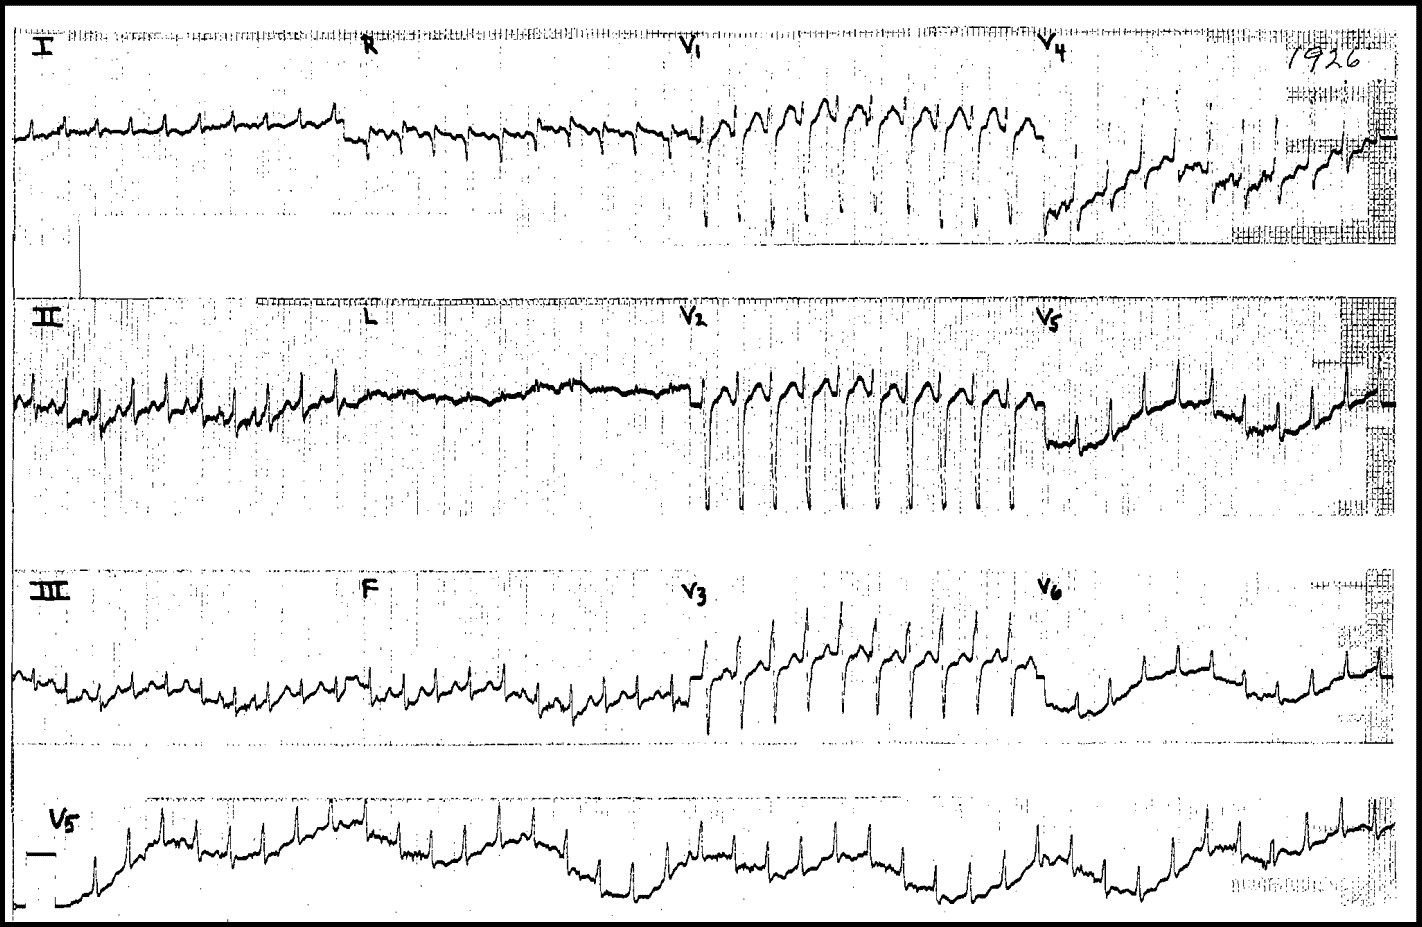

On this ECG we see Narrow Complex Tachycardia at a rate of almost 300/min.

The differential for this kind of fast tachycardia would be PSVT (AVRT ot AVNRT) and Atrial Flutter with 1:1 conduction.

You should always think of 1:1 Atrial Flutter when the rate is close to 300/min, and 2:1 Atrial Flutter when the rate is 150/min.